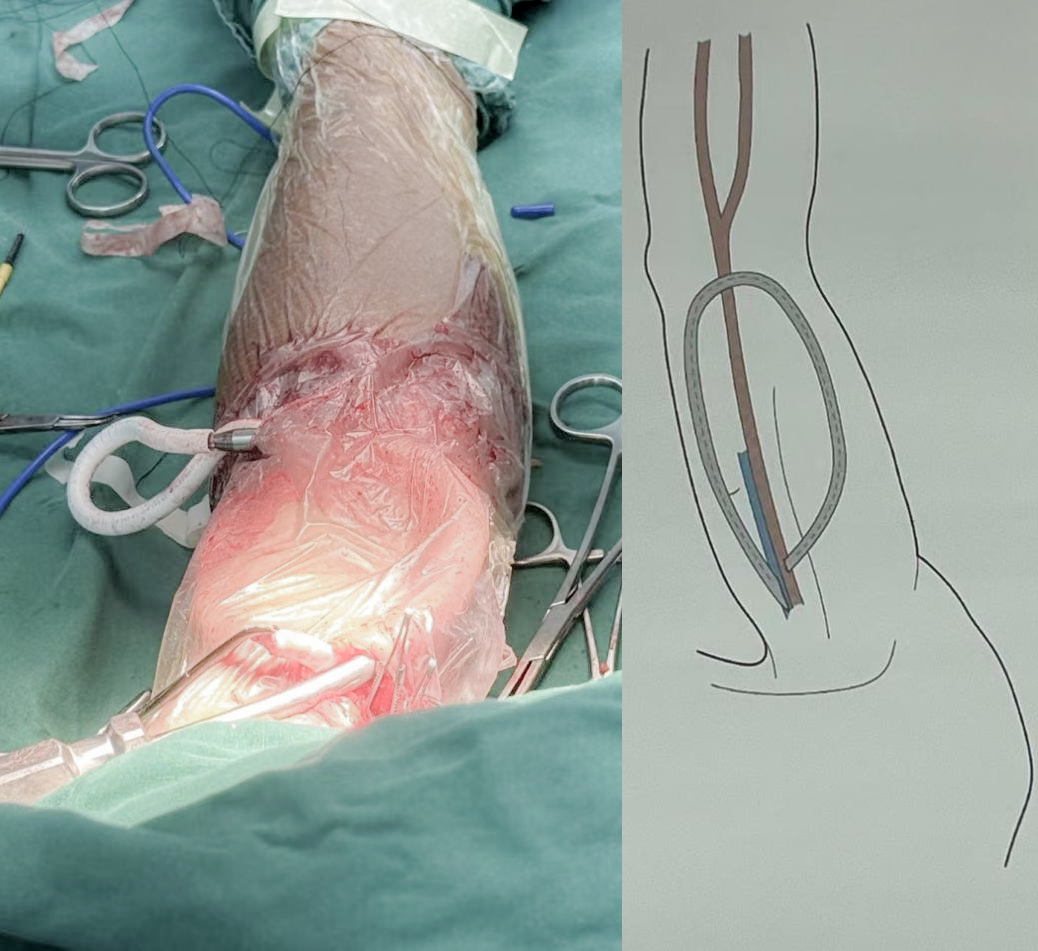

• 确定通路位置:选择上臂的肱动脉作为 “血液流入道”(为透析提供血液的动脉),相邻较粗的肱静脉作为 “血液流出道”(净化后血液回流的静脉);

• 麻醉与切口:采用臂丛麻醉(仅让上臂区域失去痛觉,降低手术痛苦),在选定血管上方做 5 厘米纵行切口,小心分离出需吻合的肱动脉与肱静脉;

• 植入人工血管:用隧道器在上臂构建 “U” 形通道,将人工血管顺利植入,确保血管走形顺畅、无压迫;

• 精准吻合:先后完成人工血管与静脉、人工血管与动脉的吻合,确保接口严密、血流无渗漏。

整台手术仅用 90 分钟便顺利完成,术后医生触摸徐大爷上臂内瘘部位,能清晰感知到动静脉内瘘震颤(轻微震动感,是内瘘血流通畅的核心标志)—— 这意味着,徐大爷的 “透析生命线” 成功打通。